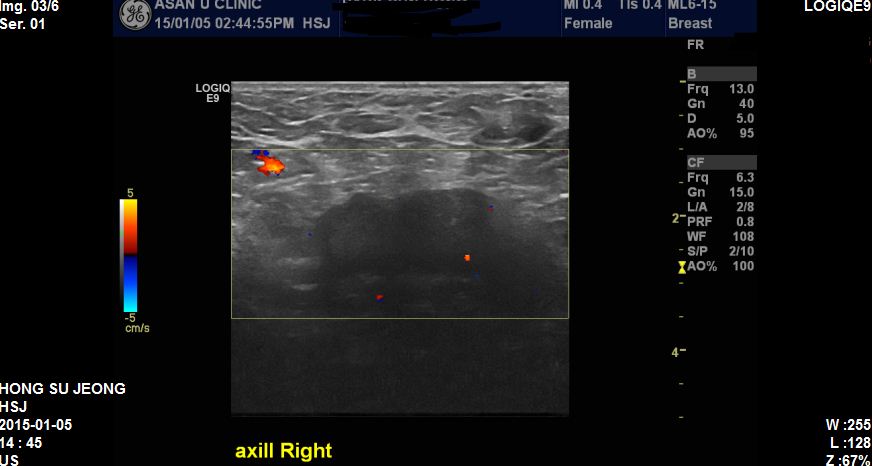

본원에서 유방초음파후 우측유방에혹과 겨드랑이 조직검사시행하였고

결과상 침윤성유방암이진단되었고 겨드랑이까지 전이된상태였습니다.